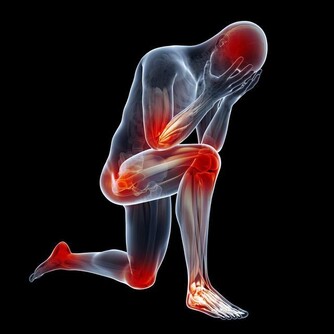

二、爬樓增加軟骨負擔

軟骨受損,幾無再生能力

雖然痛在關節,病根卻出在軟骨上。軟骨是一種濃密的膠狀物質,它不僅強壯,而且比骨頭有彈性。

正常的膝關節有一層薄薄的軟骨,它們就像骨頭與骨頭間的「潤滑劑」,如果沒有它的保護,走路時就會骨頭磨骨頭,由於骨膜上的神經和血管豐富,因而會感到非常痛。

令人遺憾的是,關節軟骨一旦受損,幾乎沒有再生能力,它沒有血管,主要靠周圍關節液提供養分。

而且,正常情況下,軟骨會隨著年齡的增長逐漸老化,

30歲後,關節軟骨的延伸能力、恢復原狀的能力開始減弱;

再加上關節液減少,關節軟骨變得乾燥,

因此人到了一定年齡,關節軟骨就容易發生損傷、磨損,引發退行性關節炎。

在我們爬山、爬樓梯的過程中,軟骨承受的壓力增加,

每上一級樓梯膝關節軟骨面將承受超過體重4倍的壓力,跑步時就更大了。

另外,爬樓梯或爬山時膝蓋除了承重增加,還要前後移動、側向扭轉,

尤其膝關節前端的髕骨部位承受壓力最大,對半月板等關節軟組織也會造成磨損。

也難怪,骨科醫生會說「有電梯絕不用樓梯」的話了。